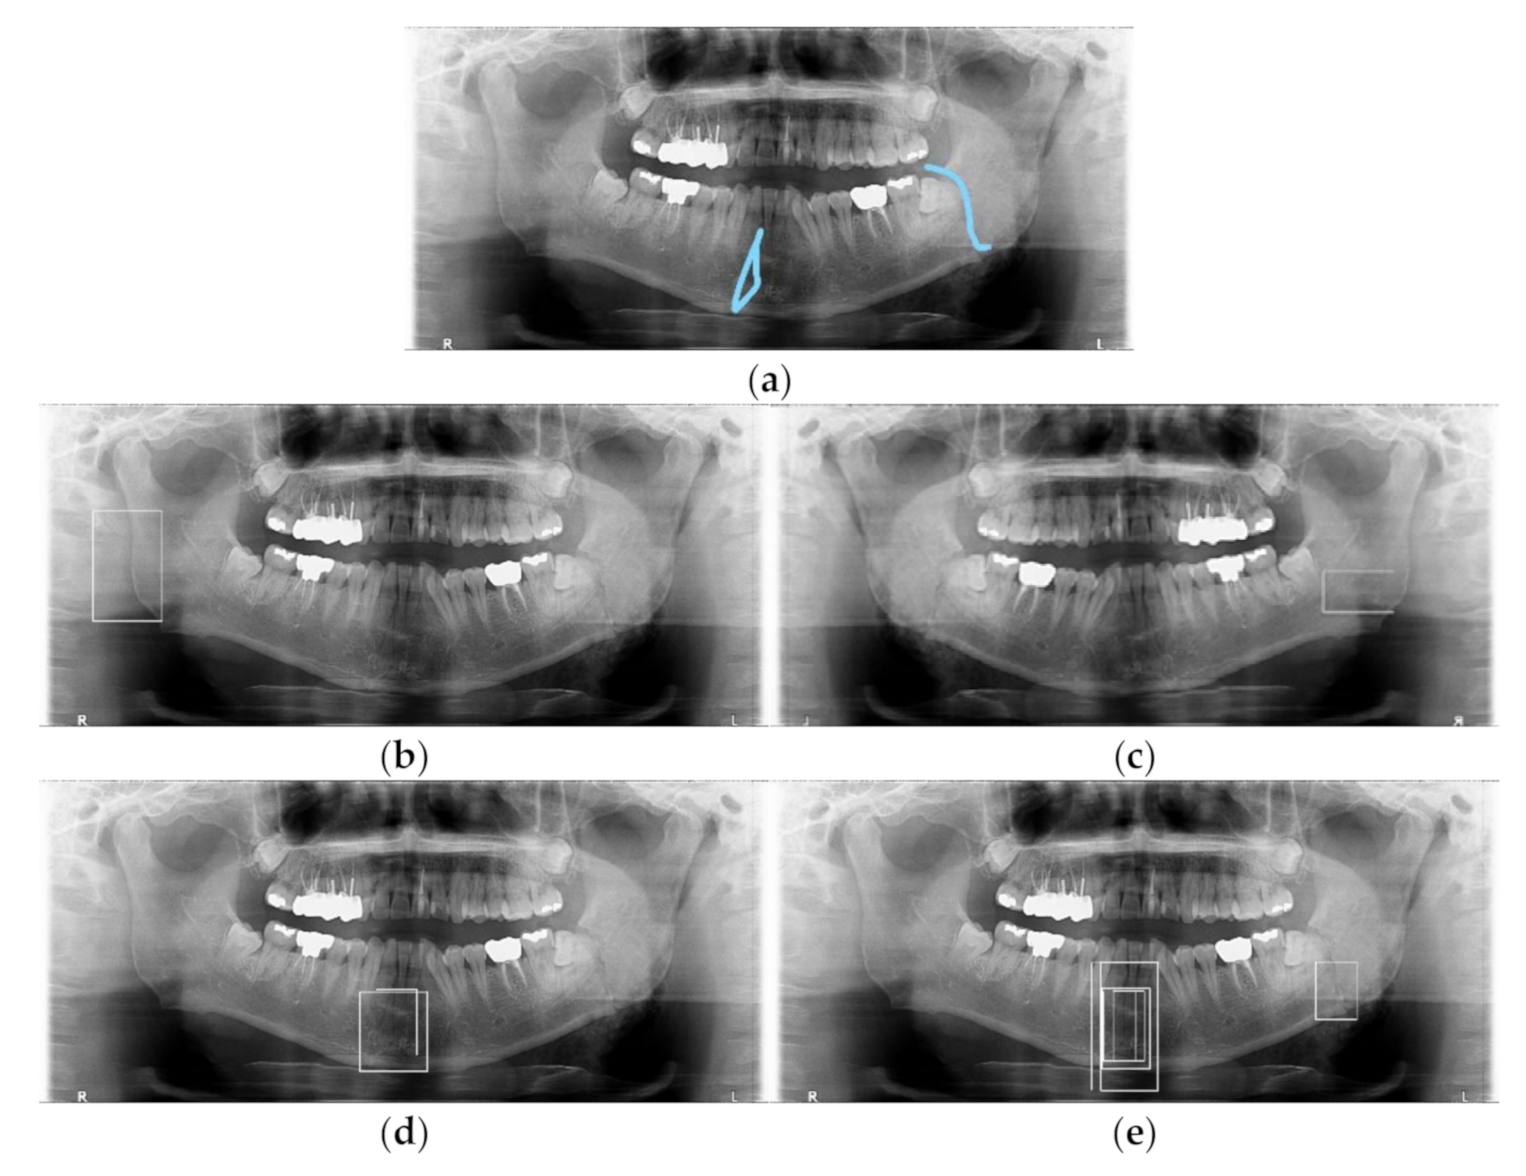

2.2.1. Data Augmentation

3.2. Detection Results